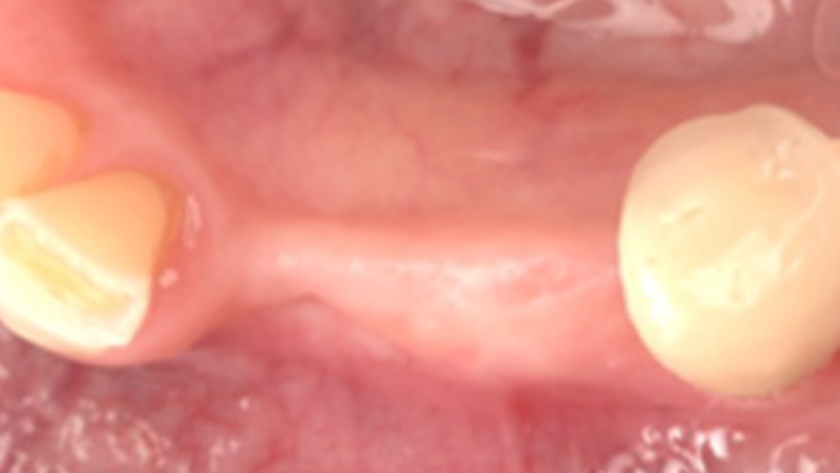

Tooth 22* required extraction in a 49-year-old female patient. The site demonstrated a Siebert Class III defect with a significant vertical discrepancy. The goal was to restore the site with an implant.